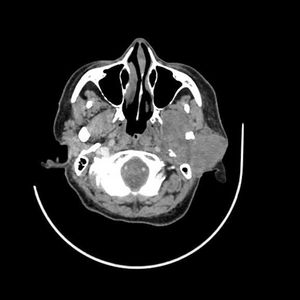

Clinical History: A 54-year-old man presented with upper lid swelling, conjunctival chemosis, and proptosis of the right eye.